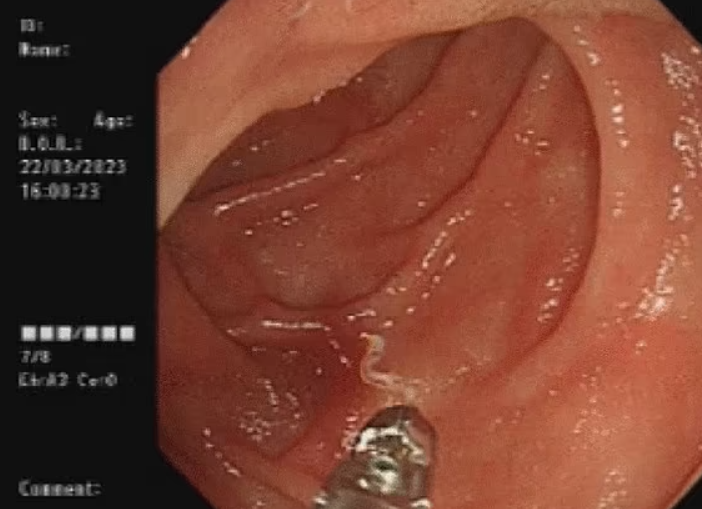

70대 여성이 식욕 부진, 불면증 등으로 병원에 갔다가 ‘아메리카구충’이라는 흡혈성 기생충에 감염된 사례. 의학저널 ‘Journal of Medical Case Reports’

대장 내시경 받다 기생충 4마리 발견

더 놀라운 건 10년 만에 재등장한 희귀 기생충이다. 경기 평택의 60대 여성이 소화불량과 변비, 설사 증상으로 내과를 찾아 대장 내시경을 받던 중 회장·맹장·상행결장 점막에서 기생충 성충 4마리가 발견됐다. 건협 메디체크연구소의 유전자 검사 결과 ‘이전고환극구흡충’으로 확인됐는데, 이는 2014년 이후 10년 만에 나타난 사례였다.

이 여성은 다슬기와 미꾸라지를 파는 노점 상인으로, 다슬기를 덜 익혀 먹은 것이 감염 원인으로 추정됐다. 특히 이 기생충은 대부분 소장에서 발견되는 일반 흡충과 달리 대장에서도 발견돼 학계의 주목을 받았다. 관련 연구는 미국 질병통제예방센터(CDC)의 학술지 ‘신종 감염병’ 2024년 8월호에 게재되기도 했다.